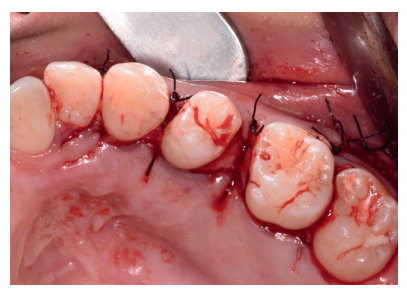

Caso clínico: se presenta un caso clínico de una mujer de 20 años, sin antecedentes médico-quirúrgicos de interés, que acudió a consulta remitida por su ortodoncista, para la extracción de un premolar maxilar retenido, en posición invertida. Tras la extracción del premolar y del tercer molar inferior retenidos, se obtuvo dentina procedente de ambos, para la regeneración ósea guiada del defecto resultante de la extracción del premolar, realizando revisiones a la semana y a los 4 meses de la intervención.

Clinical case: a clinical case of a 20-year-old woman is presented, with no interesting medical record, who went to dental clinic for removal of an inverse maxillary bicuspid retained. After maxillary bicuspid and lower third molar extractions, autogenous dentin was obtained from both teeth, to perform a guided bone regeneration of the bicuspid defect. A week and 4-month check-up were carried out.